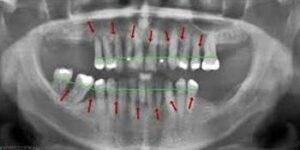

HOW ONE CAN DIAGNOSE GUM INFECTION?

Teeth are held strongly in the jaw by alveolar bone. Gum infection will lead to destruction of the bone holding the tooth. In most of the cases it happens very slowly and patients are not aware of it.